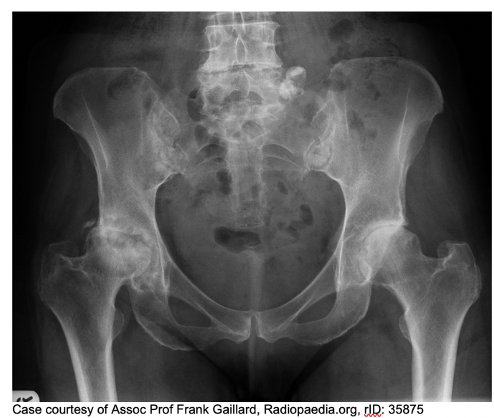

What does this show

OA of the hip

What can be done for an arthritic hip

= Initial management – Adequate pain control to ensure ongoing mobility and QoL. Lifestyle mods including weight loss, regular exercise and smoking cessation. Physiotherapy to slow disease progression.

= Long term management – if conservative don’t work them surgical intervention. Hip replacement (total or hemiarthroplasty). Common post-op complications including TE disease, bleeding, dislocation, infection, loosening of prosthesis and leg length discrepancy.

= Surgical approaches : Posterior approach, anterolateral approach, anterior approach.